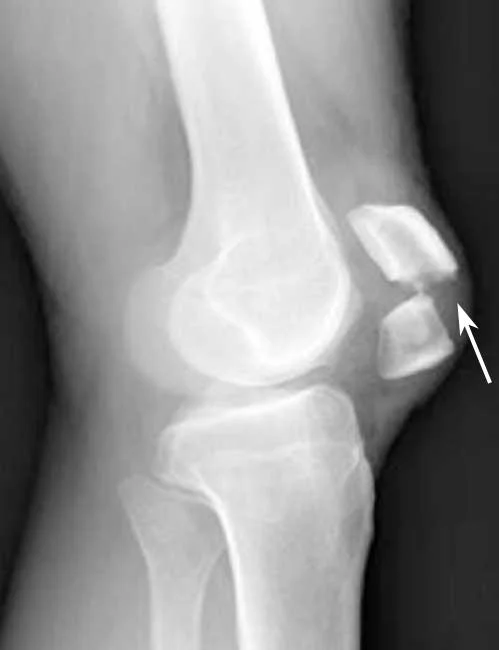

Avulsion Fractures

- Part of bone separated by forceful sudden resisted muscle action

- Caused by ligament or tendon pull on bone

- Part of bone avulsed – bone weaker than tendon/ligament